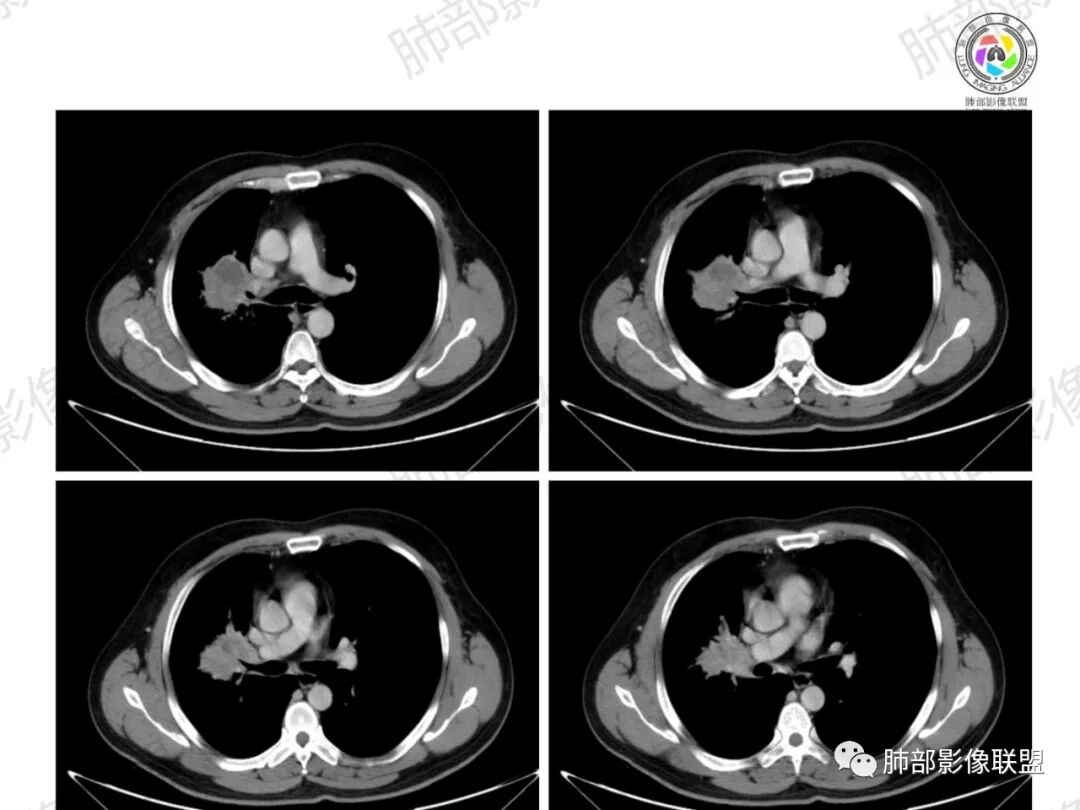

一切∮随缘:右肺门肿块影形态不规则,边缘毛糙,右肺上叶支气管堵塞,病变跨叶生长,远端血管束增粗,周围散在多发结节,部分位于胸膜下,平扫密度尚均匀,增强后不均匀强化,呈中度强化,坏死区无强化,纵隔淋巴结肿大。临床无感染症状,考虑恶性,鳞癌,腺癌,鉴别慢性脓肿。

周太狼:中年男性,吸烟史,陈旧结核史,呼吸道症状未提及,抗感染治疗无效。影像见右上肺门区软组织肿块影,浅分叶、毛刺,支气管似有截断,其内密度不均匀,不均匀强化,内可见低密度坏死区,病壮周围见斑片、结节影。纵隔内淋巴结稍肿大,首先考虑恶性,肺部肿瘤并阻塞性肺炎,肺鳞癌可能,鉴别结核。

弹指之间:中年男性,结核史、吸烟;右肺门肿块,特点:右肺上叶尖、前段支气管狭窄、部分阻塞(肿块大、支气管狭窄闭塞相对轻),肿块内血管部分残留(生长速度快,浸润>破坏),周围见渗出、炎症,部分实变;内见坏死、位于边缘区域;纵隔淋巴结肿大;考虑恶性,1.非支气管粘膜起源首先考虑,淋巴瘤?(但坏死相对多了);2.鳞癌(支气管阻塞轻);3.小细胞待排。

浅分叶,内部坏死部分边界不清,实性部分明显强化

远端有些花花草草

总觉得有部分指套改变

纵隔淋巴结肿大并不明显,就这一个肿大较明显,但仍呈椭圆形,中心少许坏死。